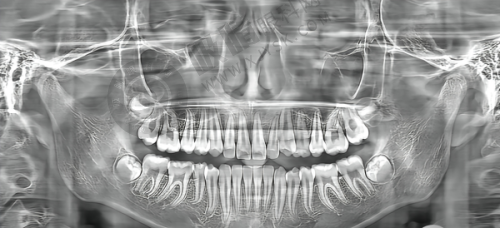

种植牙项目:采用ZDI种植系统,有表面处理技术、数字化种植、即刻修复方案等技术升级。无论是单颗牙缺失,还是半口、全口牙缺失,都能在这里得到良好的解决。单颗种植成功几率非常高,半口/全口种植年均完成200例,对于复杂病例处理(上颌窦提升 + 骨增量联合手术)也有较高的成功几率。

在种植牙领域,其采用的ZDI种植系统带来了一系列技术升级。表面处理技术能让种植体更好地与牙槽骨结合;数字化种植使得种植过程更加精细;即刻修复方案则大大缩短了患者缺牙的时间。这些技术的应用,确保了单颗种植的高成功几率,也让半口、全口种植以及复杂病例的处理更加得心应手。